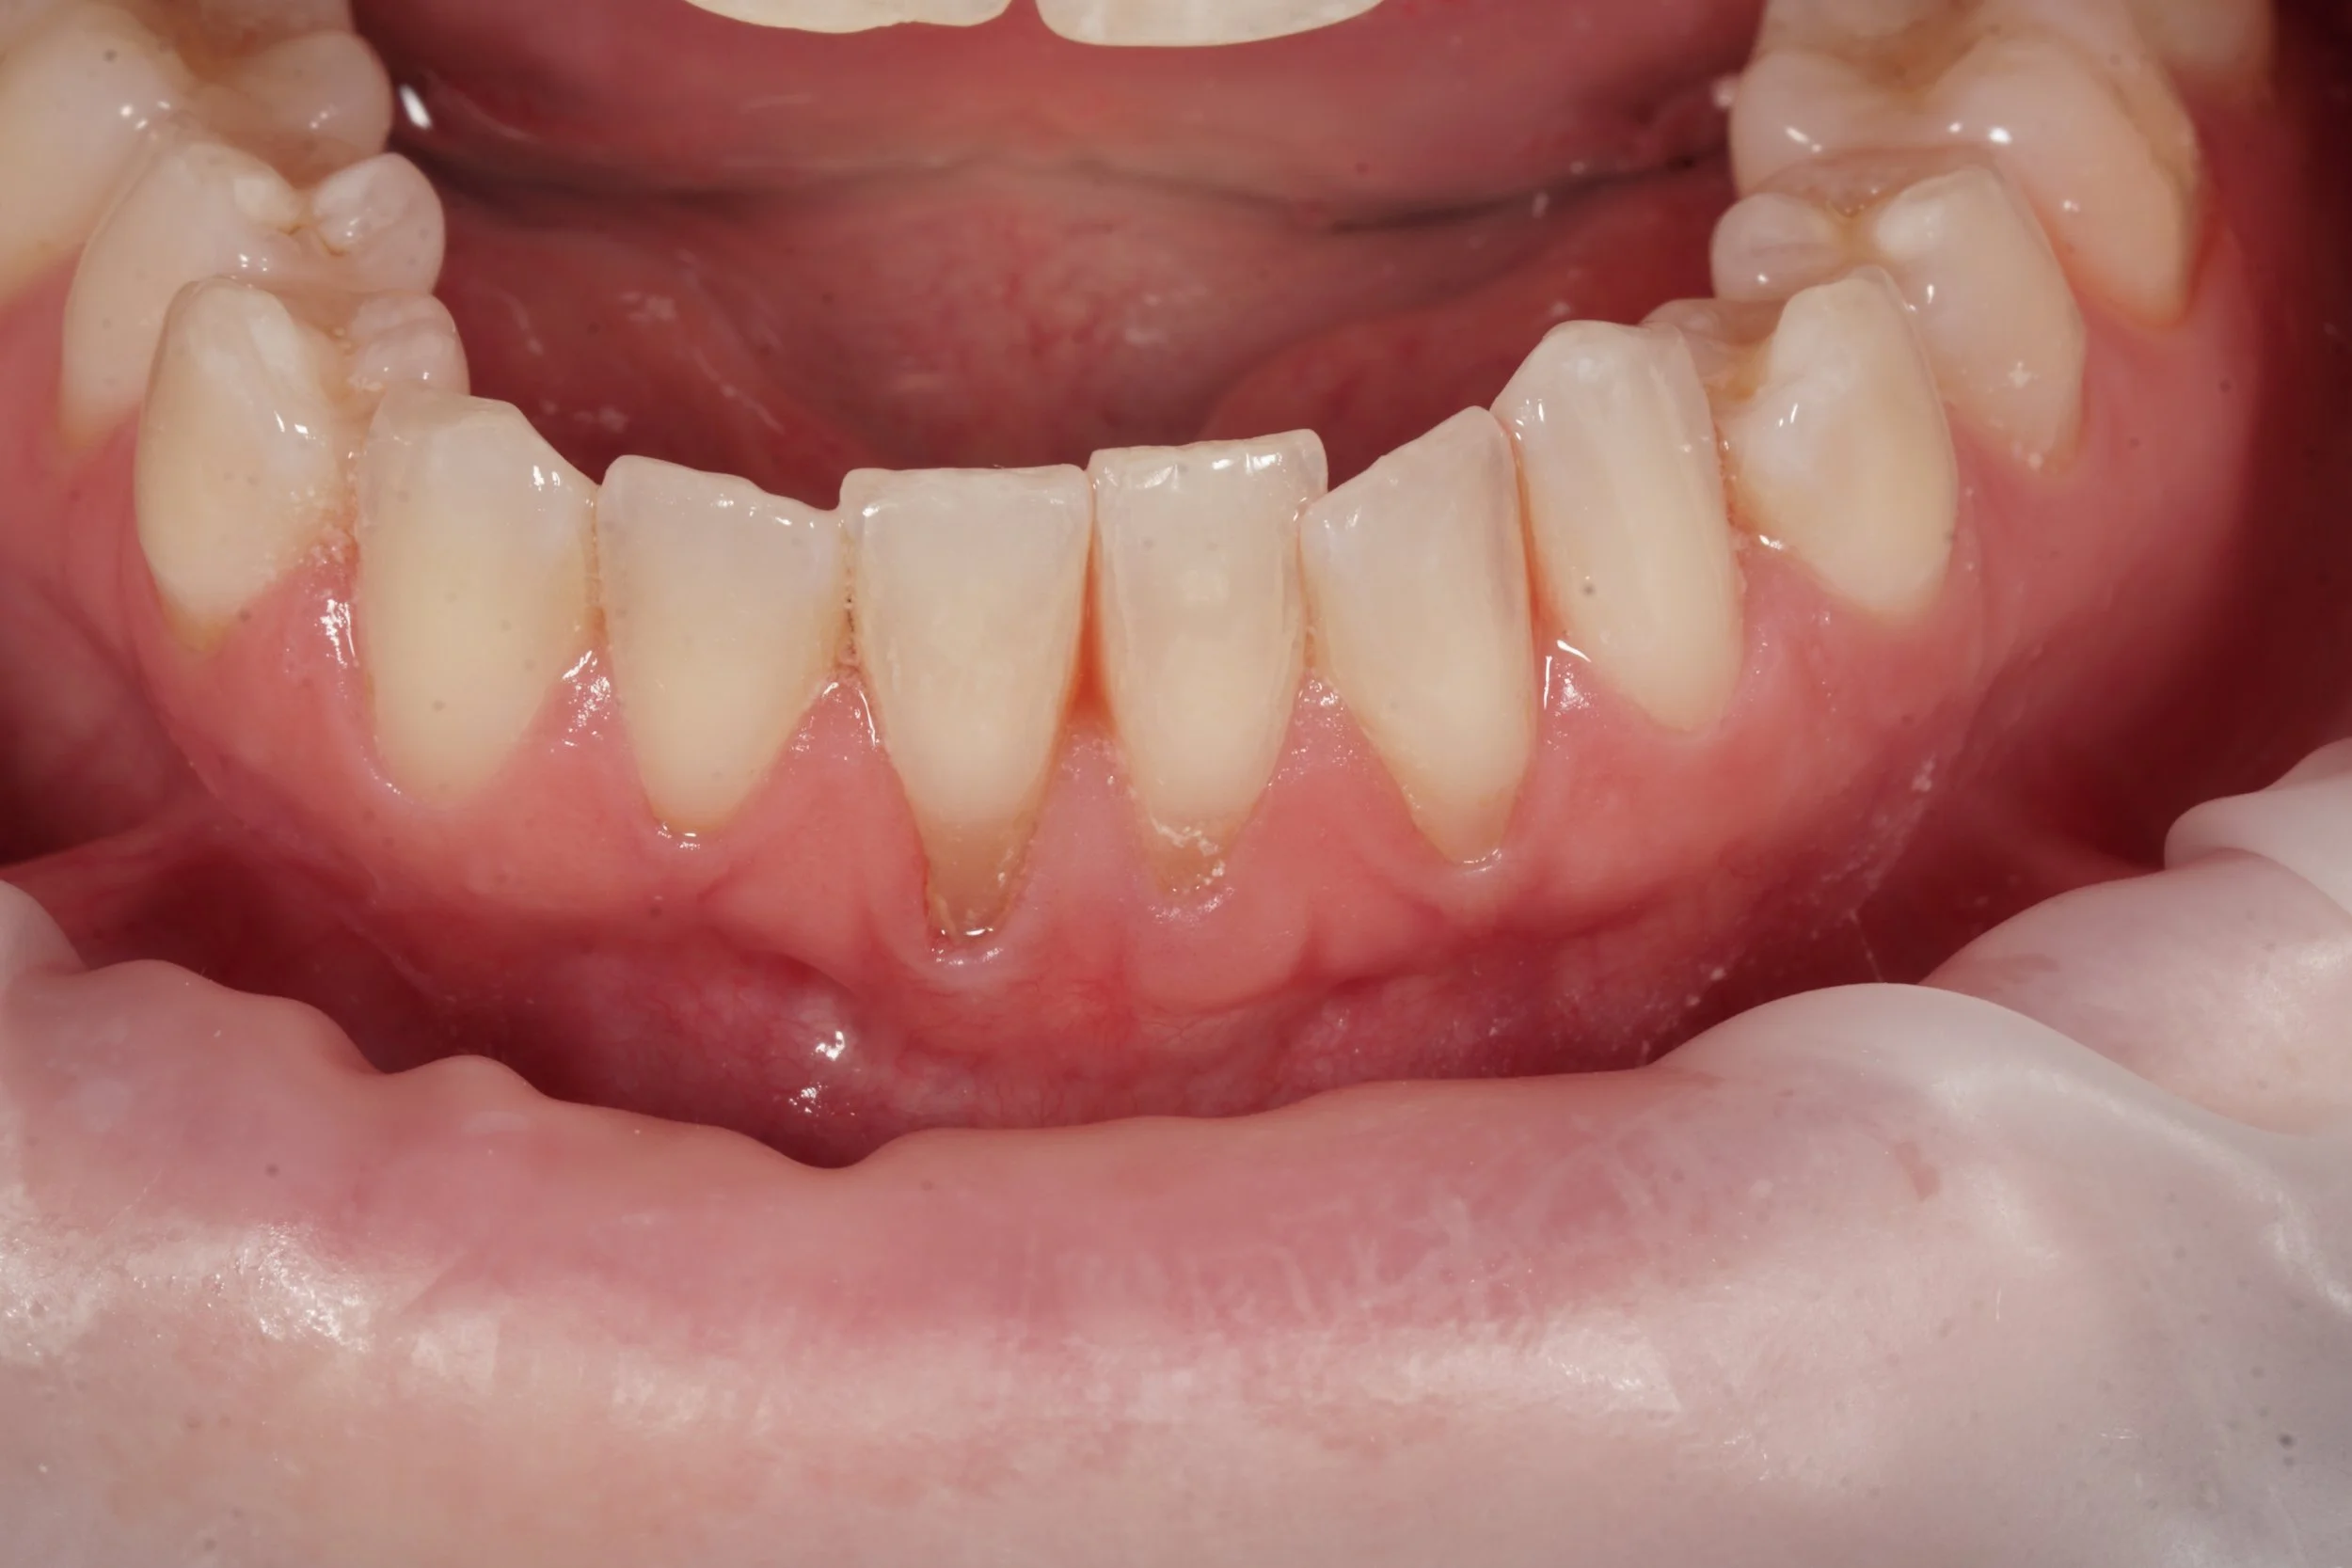

Significant recessions and root exposure of lower incisor teeth. Due to root exposure, patient's cleansing was impaired causing gum inflammation, gingivitis

Significant recessions and root exposure of lower incisor teeth. Another problem shown in this image is thin gingival biotype, thin gum tissue, leading to further recession.